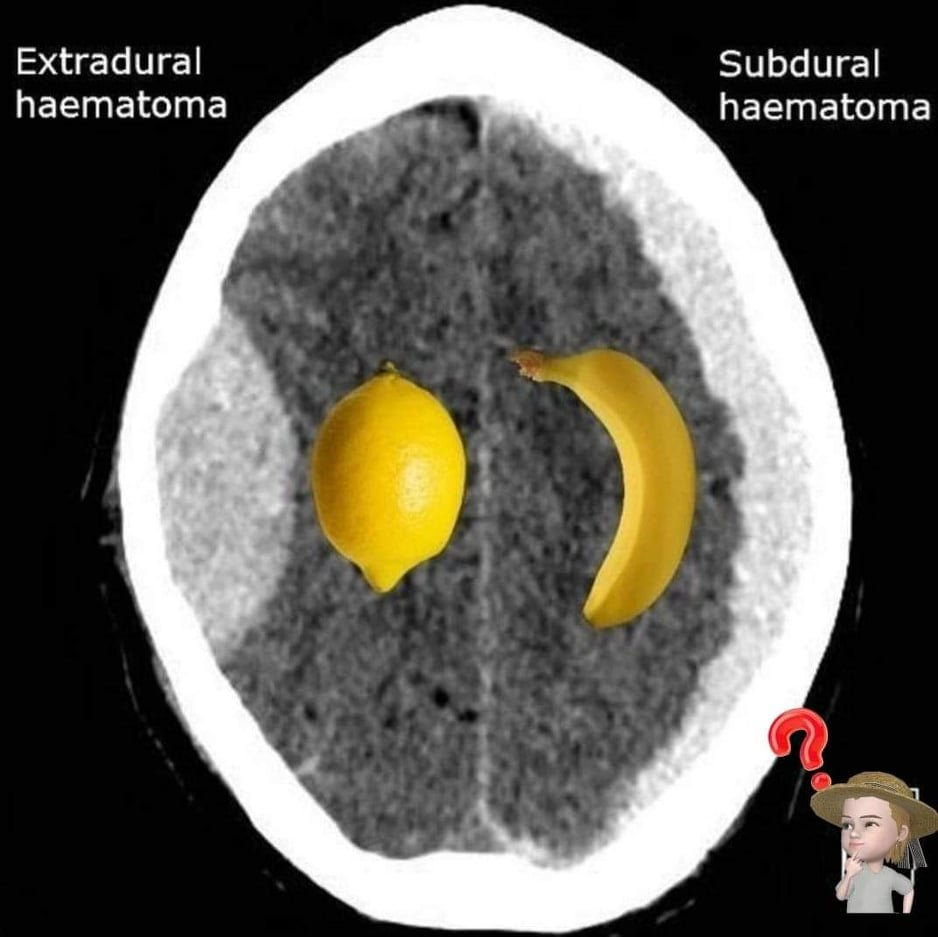

Lămâie sau banană? Neurologii nu doresc să le vadă pe imaginile de CT cerebral!

Lămâie sau banană? În neurologie, nu preferăm niciunul dintre aceste fructe atunci când le întâlnim silueta pe o imagine de CT cerebral.

Silueta unei banane o vizualizăm atunci când este vorba despre un hematom subdural, adică o sângerare ce survine ca urmare a unui traumatism. Creierul este învelit în 3 „foițe” (pia mater, arahnoida și dura mater).

Hematomul subdural („banana”) este o acumulare de sânge localizată între dura mater și creier, el apare ca urmare a rupturii cel mai adesea post traumatice a unui mic vas de sânge din acea zonă și poate da diverse manifestări neurologice în funcție de cât de mare este și cât de mult comprimă creierul (de la simplă durere de cap până la comă).

Ca și în lumea fructelor, și în neurologie lămâia e mult mai acră decât banana, adică un hematom extradural e mai grav și mai riscant decât unul subdural. Hematomul extradural reprezintă o acumulare de sânge între cutia craniană și dura mater și îl întâlnim de regulă tot postraumatic, mai ales la pacienții tineri (mai rar peste 60 de ani la care dura mater aderă mai strâns la os). De regulă el reprezintă o mare urgență neurochirurgicală, deoarece poate crește rapid în volum și antrena nu doar deficite neurologice, ci și comă și moarte din cauza fenomenului de angajare cu compresie pe trunchiul cerebral (zona din creier unde sunt centrii nervoși ce ne coordonează funcțiile vitale).